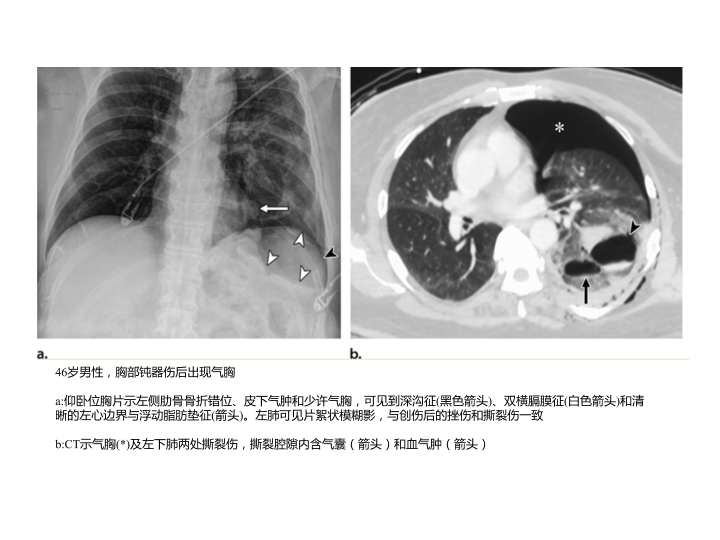

胸部外伤及胸腔积液处理